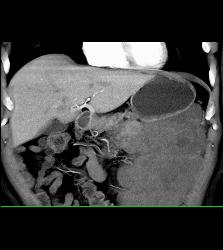

Diagnosis

GIST Tumor